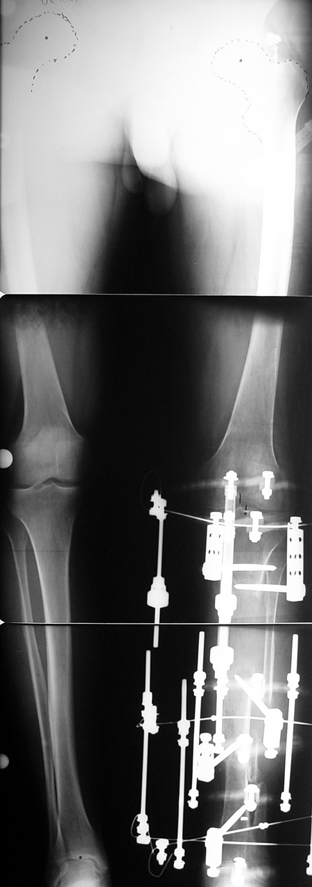

Appropriate radical debridement necessitates excision of all necrotic bone and soft tissues, and frequently causes instability at the involved extremity. The remaining bone and soft tissue defect has to be fixed and reconstructed. The distraction osteogenesis method of Ilizarov is used successfully for achievement of union, correction of the deformity, elimination of limb length inequality and reconstruction of segmental bone defects.

The duration of external fixation (external fixation index) depends on the amount of distraction required, and the extremity is prone to complications during this period. After the distraction phase is completed, the external fixator remains in place during the consolidation phase, which lasts twice as long as the distraction phase; but this period is hardly tolerated. If the external fixator is removed before sufficient consolidation is achieved, fractures, deformity and shortness will be the result. In our department, ‘lenghthening over nail’ method is used in order to decrease the external fixation index and increase patient comfort and activity level. In this method, the intramedullary nail is statically locked after the completion of the distraction phase, and external fixator is removed. The extremity is stabilized by the intramedullary nail during consolidation phase. In this way, complications due to long external fixation index or early removal of the external fixator are avoided.

Case 2